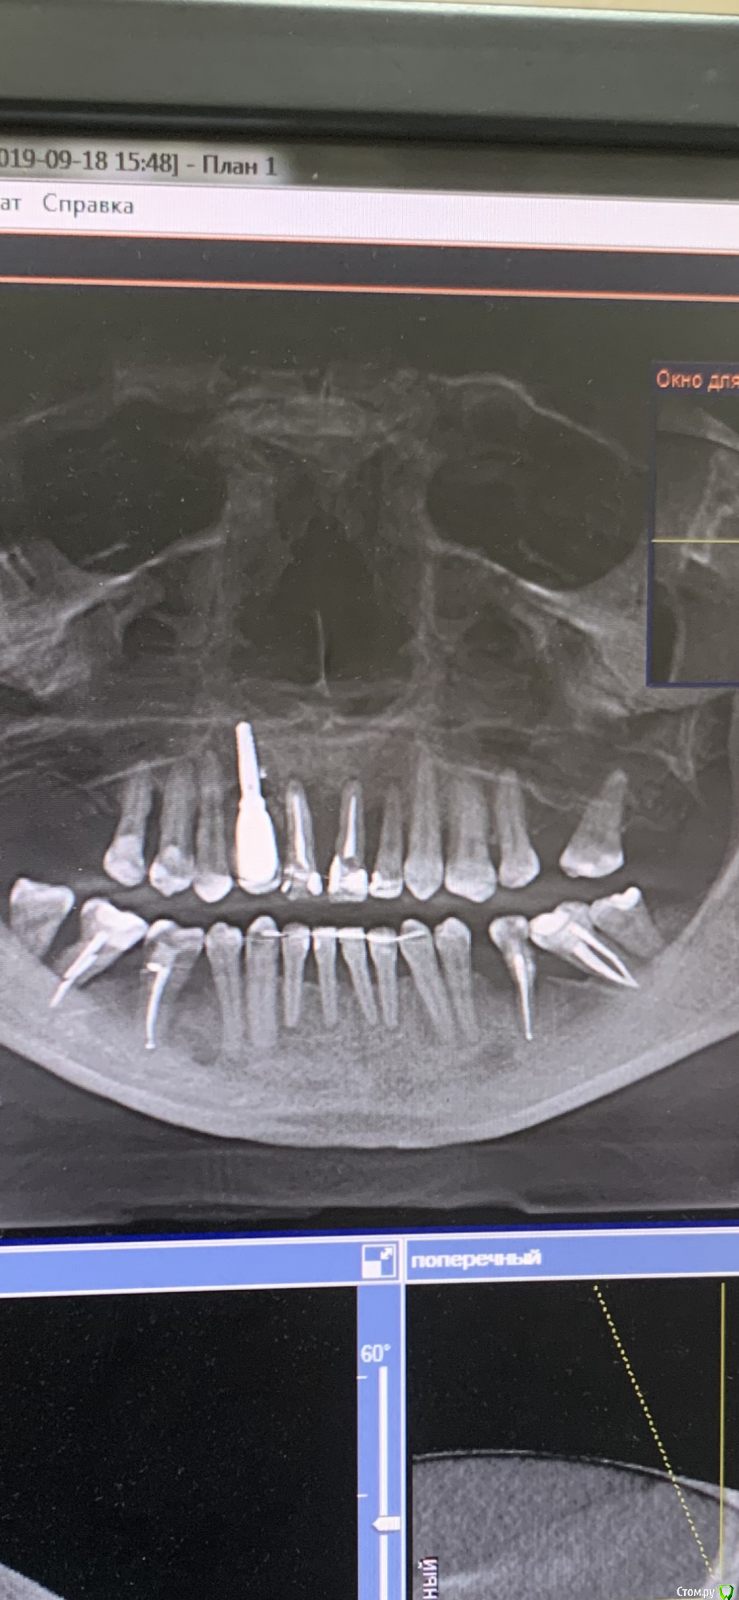

pavlin Опубликовано 12 ноября, 2019 Поделиться Опубликовано 12 ноября, 2019 (изменено) Планируется удаление 11 21 22 и имплантация в этой обл . Импланта в обл 12 ставили в др клинике несколько лет назад . Вопрос - тк кость в обл зубов ушла практически полностью , ставить Имплант как вОбл 12 (до носовой пазухи 8 мм ) тогда колонковая часть получается огромной ? Изменено 12 ноября, 2019 пользователем pavlin Ссылка на комментарий

Irouil Опубликовано 13 ноября, 2019 Поделиться Опубликовано 13 ноября, 2019 Вам нужно растолковать? Планируйте с ортопедом работу, я не сказал, что эта работа а) обязательно несъемная б) обязательно на имплантатах Для этого надо изучить кт (а не эти ужасные ошметки, извините, что Вы предоставили), осмотреть пациента, получить от ортопеда добро на количество и позиции имплантатов в случае их использования. Колесников Вам сразу написал - планируйте тотальную реабилитацию пациента. Вероятнее всего, на верхней челюсти тут встают 3 винта (один уже есть) и через полгода встают ещё 2. Либо на 4. Ссылка на комментарий

колесников Опубликовано 13 ноября, 2019 Поделиться Опубликовано 13 ноября, 2019 Этот имплант-ошибка. Не повторяйте чужих ошибок. Закопать его и забыть 1 Ссылка на комментарий